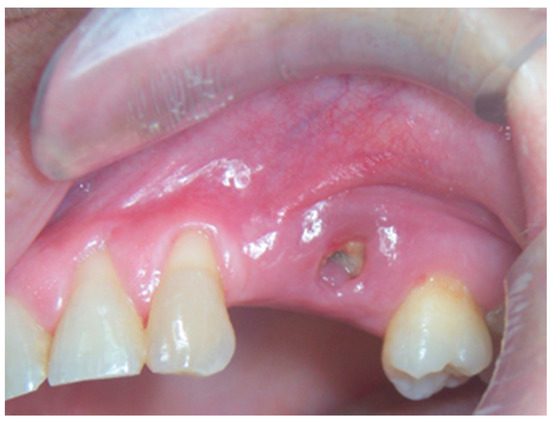

2. Materials and Methods

3. Results

4. Discussion